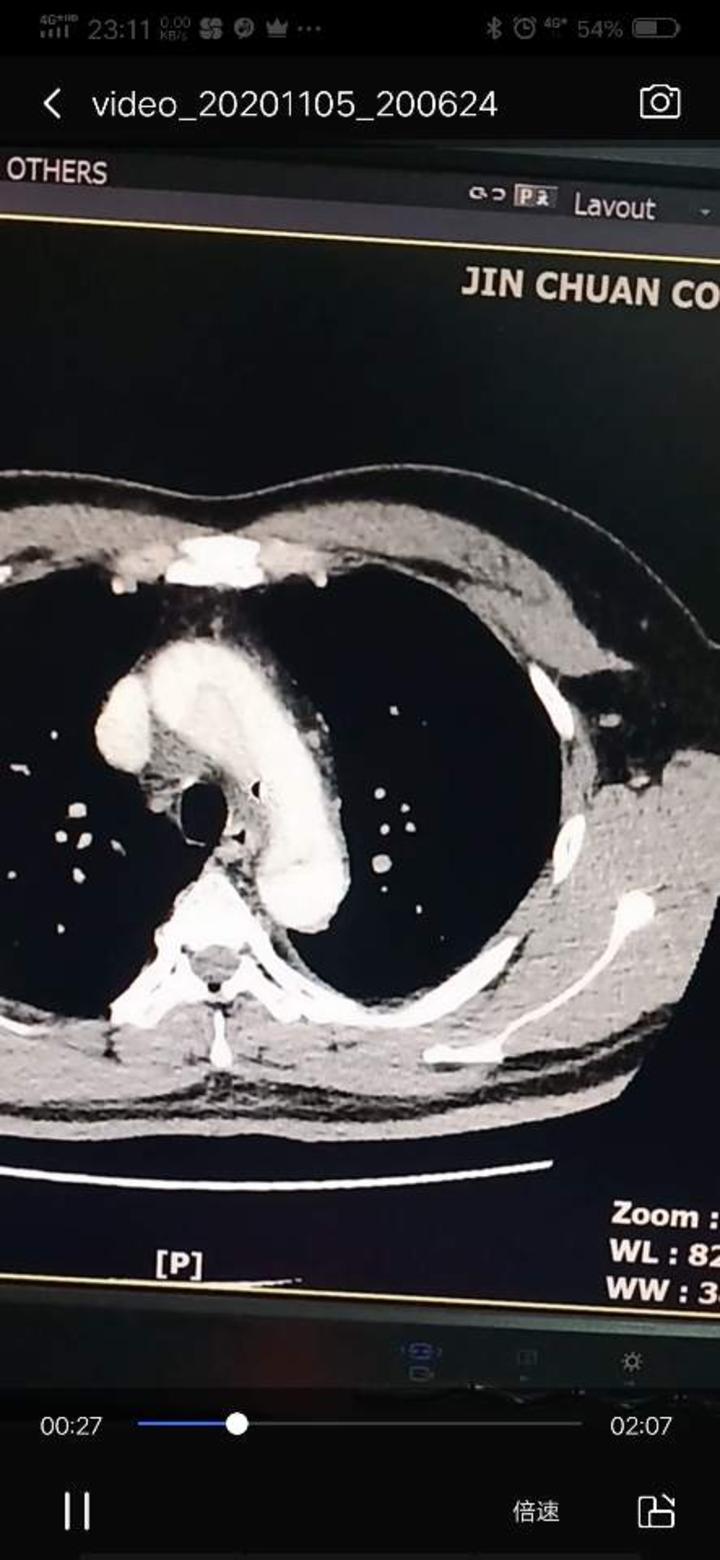

分享主动脉夹层cta